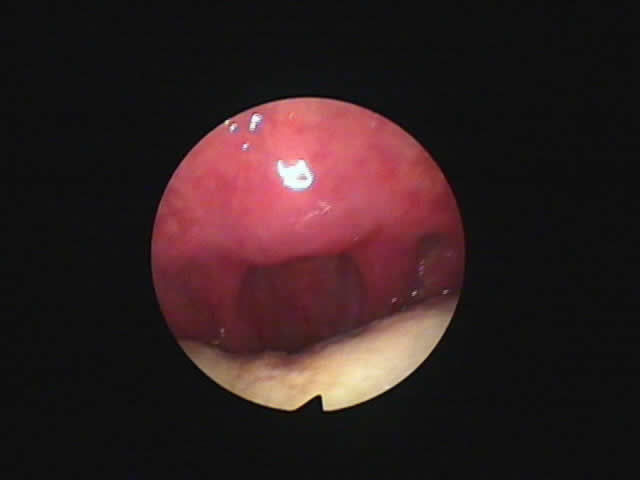

1) 手術前、口蓋垂(のどちんこ)が太く長く舌にくっついており、その横の粘膜も幅が広い。いびき改善手術をすることとなりました。 2) 外来(日帰り手術)手術後50日、70%のいびき音が改善したと本人がいっております。のどがひろくなりました。